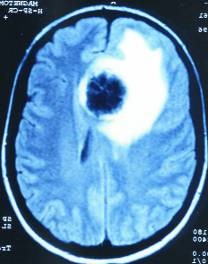

Für uns stellt diese zufällig gemachte Kernspintomographie einen wissenschaftlichen „Glücksfall“ dar, weil uns Kernspinaufnahmen, die nach solch langer Konfliktdauer in der gerade beginnenden Heilungsphase zufällig genau im „richtigen Moment“ gemacht worden sind, ein außergewöhnlich gut sichtbares Phänomen demonstrieren (mit Kontrast links, ohne rechts):

Wir sehen im Inneren des gerade in Lösung gehenden großen Hamerschen Herd (HH) noch die alten Schießscheibenringe, die nur noch kurz so gut zu sehen sind, weil sie dann im Oedem verschwimmen.

Normalerweise können wir mit dem Kernspin-Tomogramm Schießscheibenringe des HH erst nach 2 bis 3 Jahren Konfliktdauer erkennen. Und dann färben sie sich ja auch nicht mit Kontrastmittel an.

Hier aber hat der Radiologe zufällig den richtigen Tag erwischt und zufällig auch die richtige Aufnahmetechnik, mit Kontrastmittel.

Die Schießscheibenringe tauchen noch einmal wieder auf und färben sich in der pcl-Phase weiß an, um dann meist im Oedem zu verschwimmen.

Auf der rechten Aufnahme ohne Kontrastmittel ist praktisch kein Ring zu sehen.